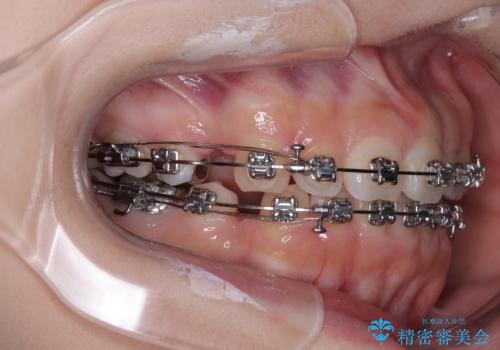

- メタルブラケット

- 2年2ヶ月

- 10-30回

しかしながら、唇を閉じたときに口元に緊張感があり、そのまま叢生を解消すると横顔が突出した印象になる可能性が高かったため、上下左右の小臼歯4本を抜歯して、ワイヤー装置にて矯正治療を行うこととしました。

矯正治療後には、目立っていた奥歯の銀歯をオールセラミッククラウンへ作り替え、スッキリした口元に仕上がりました。